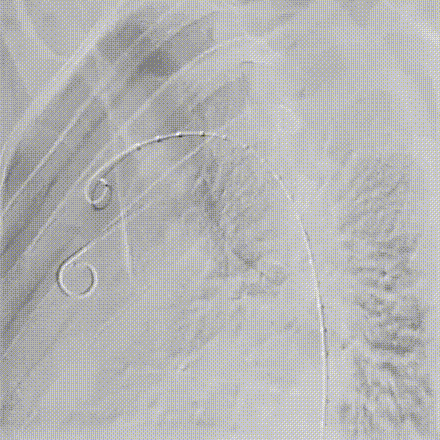

5.第二次拉线释放后支架从远端至近端打开至全直径,支架位置精准形态良好,微调角度控制旋钮,使支架小弯侧贴壁更佳。完成后续释放操作后进行主动脉弓部造影。

gore医疗怎么样「胸有乾坤」可调可控 分毫必争—GORE®TAG® 可主动调控胸主动脉覆膜支架治疗B型主动脉夹层伴升主动脉瘤病例报道_https://www.jmylbn.com_新闻资讯_第11张

全直径释放

gore医疗怎么样「胸有乾坤」可调可控 分毫必争—GORE®TAG® 可主动调控胸主动脉覆膜支架治疗B型主动脉夹层伴升主动脉瘤病例报道_https://www.jmylbn.com_新闻资讯_第12张

主动调控支架小弯侧贴壁